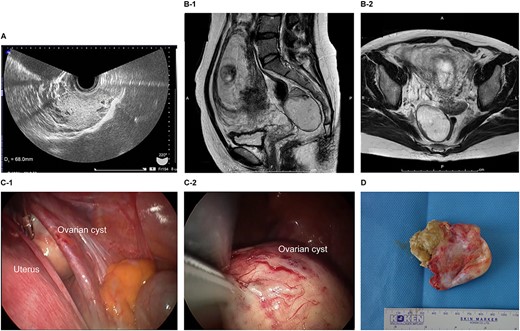

The patient was a 40-year-old, gravida 1, para 0 woman with no familial or medical history. She conceived naturally and was diagnosed with a left ovarian cyst at 5 weeks gestation by another doctor. She was referred to our hospital for further examination and operation. TVUS revealed a fetus in the uterus and a mass 6 cm in diameter on the left ovary, which appeared to be a dermoid cyst. MRI revealed left ovarian cystic tumors with fat tissue. The laboratory values, including the levels of tumor markers (e.g. CEA, CA-125, CA 19–9 and SCC) were within the normal limits. We performed single-port laparoscopic surgery at 17 weeks and 0 days gestation to remove the left ovarian cysts. The procedure was performed within 59 minutes, and there were no complications (Fig. 2).

Imaging studies and laparoscopic views and specimen photograph of case 2. (A) Transvaginal ultrasound image showing an ovarian cyst. (B-1) Sagittal T2-weighted magnetic resonance image (MRI) showing an ovarian cyst. (B-2) Axial T2-weighted MRI showing an ovarian cyst. (C-1) Gestational uterus: ovarian cyst was moved from the pouch of Douglas. (C-2) Ovarian cyst was moved and located on the gestational uterus. (D) Ovarian Cyst.